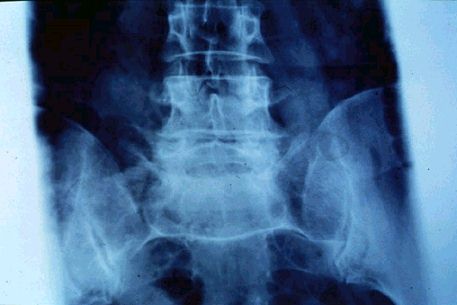

Aspecto radiológico de una espondiloartrosis degenerativa de columna lumbar.